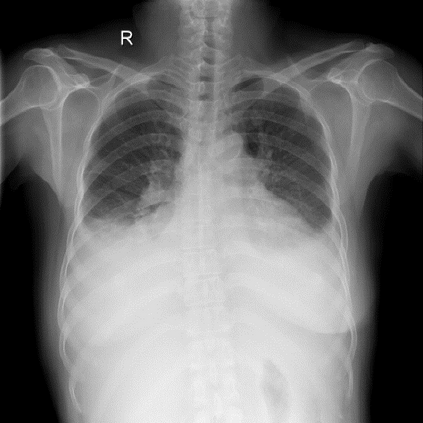

Chest X-ray (CXR) is the most typical diagnostic X-ray examination for screening various thoracic diseases. Automatically localizing lesions from CXR is promising for alleviating radiologists' reading burden. However, CXR datasets are often with massive image-level annotations and scarce lesion-level annotations, and more often, without annotations. Thus far, unifying different supervision granularities to develop thoracic disease detection algorithms has not been comprehensively addressed. In this paper, we present OXnet, the first deep omni-supervised thoracic disease detection network to our best knowledge that uses as much available supervision as possible for CXR diagnosis. We first introduce supervised learning via a one-stage detection model. Then, we inject a global classification head to the detection model and propose dual attention alignment to guide the global gradient to the local detection branch, which enables learning lesion detection from image-level annotations. We also impose intra-class compactness and inter-class separability with global prototype alignment to further enhance the global information learning. Moreover, we leverage a soft focal loss to distill the soft pseudo-labels of unlabeled data generated by a teacher model. Extensive experiments on a large-scale chest X-ray dataset show the proposed OXnet outperforms competitive methods with significant margins. Further, we investigate omni-supervision under various annotation granularities and corroborate OXnet is a promising choice to mitigate the plight of annotation shortage for medical image diagnosis.